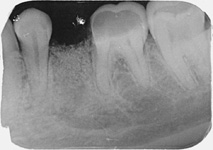

Nejlepším materiálem pro augmentace je vlastní kost pacient, kterou můžeme získat

např. odběrem z dolní čelisti pacienta. Jedná se o velmi šetrný, nenáročný výkon, který pacienta nijak nezatíží.

Kostní biomateriály BEGO

Pokud je potřeba většího množství kosti na doplnění, poskytujeme našim pacientům nejkvalitnější náhradní kostní materiály přírodní i syntetické od firmy BEGO.

K překrytí, doplněné kosti, se používají různé typy kolagenních membrán nebo kortikálních lamin